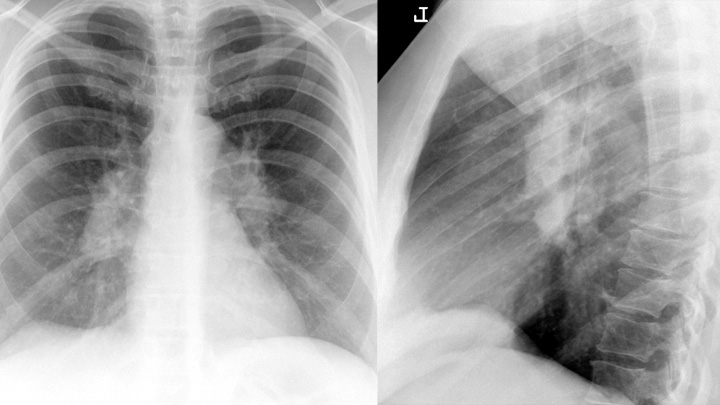

Gallery Sarcoid Sarcoid Case 1 PA & Lat

Case 1 PA & Lat